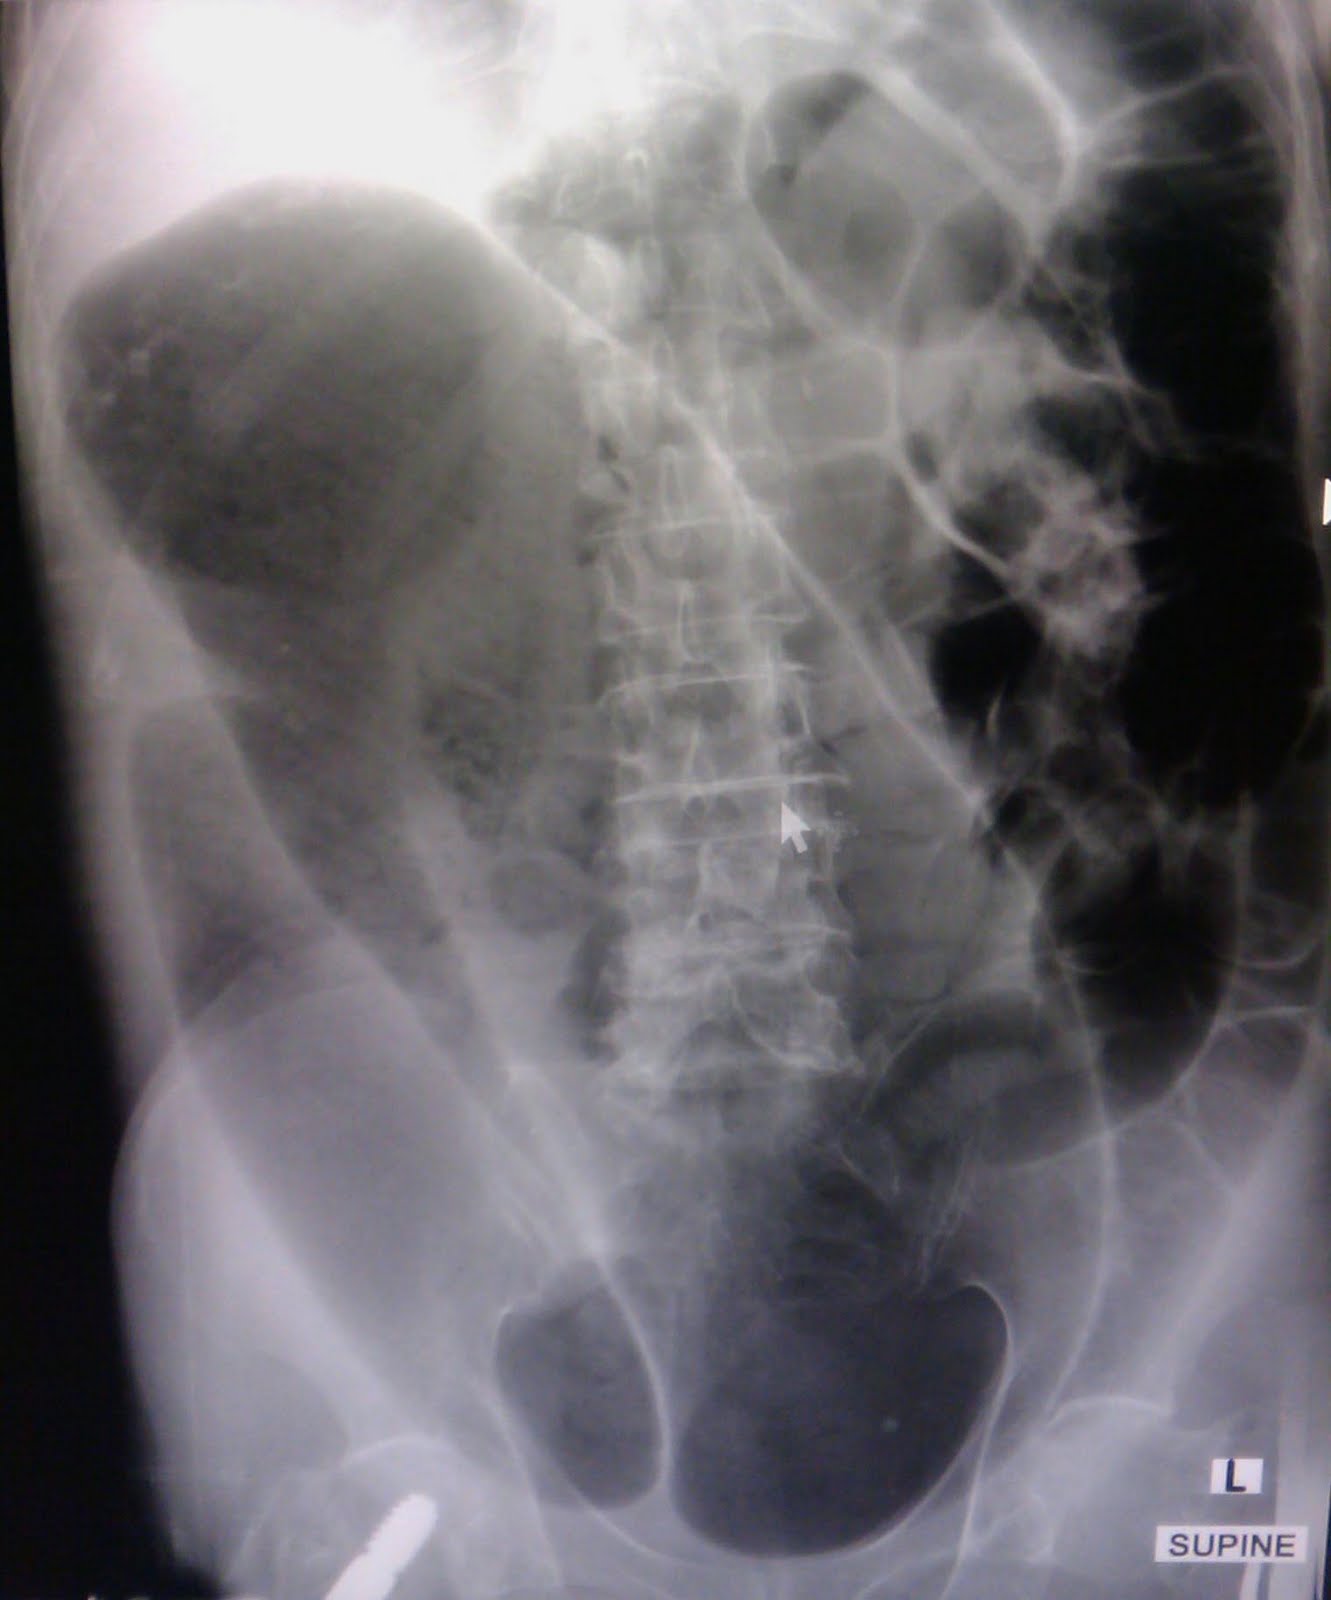

XRay Abdomen (supine) showing the Coffee Bean appearance of Sigmoid Colon. Download Coffee Bean Bowel X Ray the coffee bean sign is a radiological sign used to describe the twisting of the sigmoid colon about its. there are several classic signs describing the findings of colonic volvulus; The coffee bean sign describes the appearance of the volvulus, with apposition of the medial walls of the dilated loop of bowel forming the cleft of the bean. Coffee Bean Bowel X Ray.

Coffee Bean Bowel X Ray . The coffee bean sign describes the appearance of the volvulus, with apposition of the medial walls of the dilated loop of bowel forming the cleft of the bean and the lateral walls forming the outer walls of the bean. Sigmoid volvulus is due to a twist at the base of the sigmoid mesentery which is in a fixed position (asterisk) in the left iliac fossa. the coffee bean sign (also known as the kidney bean sign or bent inner tube sign) 4 is a radiological finding on an abdominal. This results in the appearance of a giant 'coffee bean', the typical sign of sigmoid volvulus. the coffee bean sign is a radiological sign used to describe the twisting of the sigmoid colon about its. These include the coffee bean and bird beak signs. there are several classic signs describing the findings of colonic volvulus; The sigmoid colon is very dilated because it is twisted at the root of its mesentery in the left iliac.